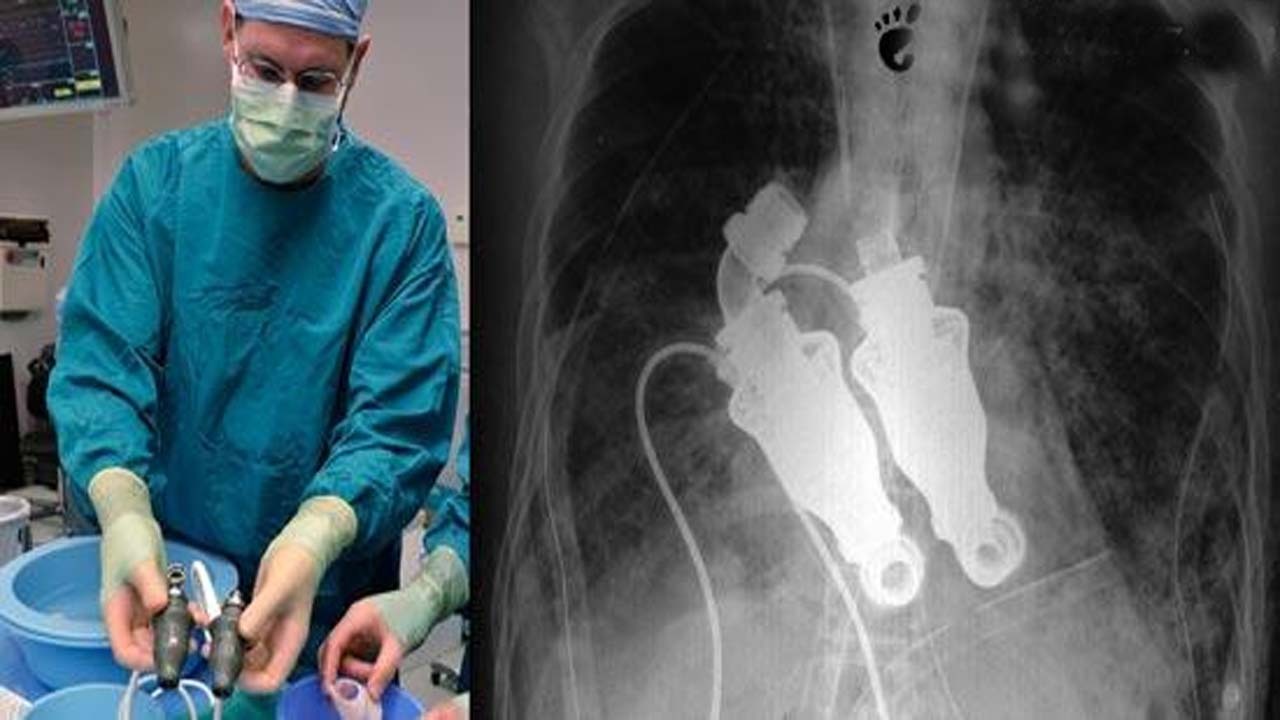

وسیله‌ای که به جای قلب در سینه کرگ کارگذاشته شد شبیه توربینی است که نقش موتور‌های چرخش سریع خون را دارد و برای اینکه این وسیله بتواند خون را در بدن به جریان بیندازد مجهز به بخش‌هایی شبیه به تیغه‌های پهن است.

البته بیماران دیگری از جمله دیک چنی معاون رئیس‌جمهور سابق آمریکا هم، وسیله‌ای شبیه به چیزی که به جای قلب در سینه کرگ کار گذاشته شد دارند با این تفاوت که این وسیله روی یکی از بطن‌های آن‌ها کار گذاشته شده و کمک می‌کند تا قلب ضربان داشته باشد و بتواند خون را در بدن به گردش درآورد.